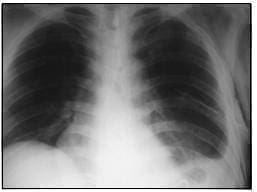

Se procedió a practicar gastrectomía subtotal con reconstrucción en Y de Roux y herniorrafia diafragmática con sutura de material no absorbible, paso de sonda con punta de tungsteno y colocación de tubo en el tórax izquierdo. Se obtuvo radiografía de tórax de control postquirúrgico (figura 4) con adecuada reexpansión pulmonar.

FIGURA 4. Radiografía de tórax (control postquirúrgico). Derrame pleural izquierdo escaso, con tubo de toracostomía cerrada en el hemitórax izquierdo, y enfisema subcutáneo; el aspecto anatómico de las estructuras está dentro de los límites normales.